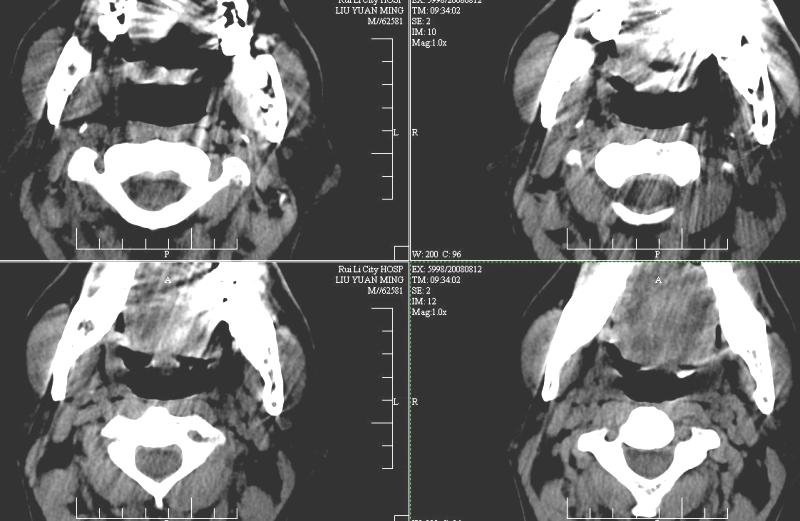

以下是引用ydx_74在2008-8-12 22:09:00的发言:[br]不考虑鼻咽癌。没有淋巴结肿大,没有颅底骨质破坏,咽隐窝、咽鼓管咽口存在,咽旁间隙清楚,平扫ct值34hu,增强动脉期81hu,实质期约85hu,增强幅度达50多,除外增强时机没有掌握好因素,可以考虑鼻咽纤维血管瘤吗?